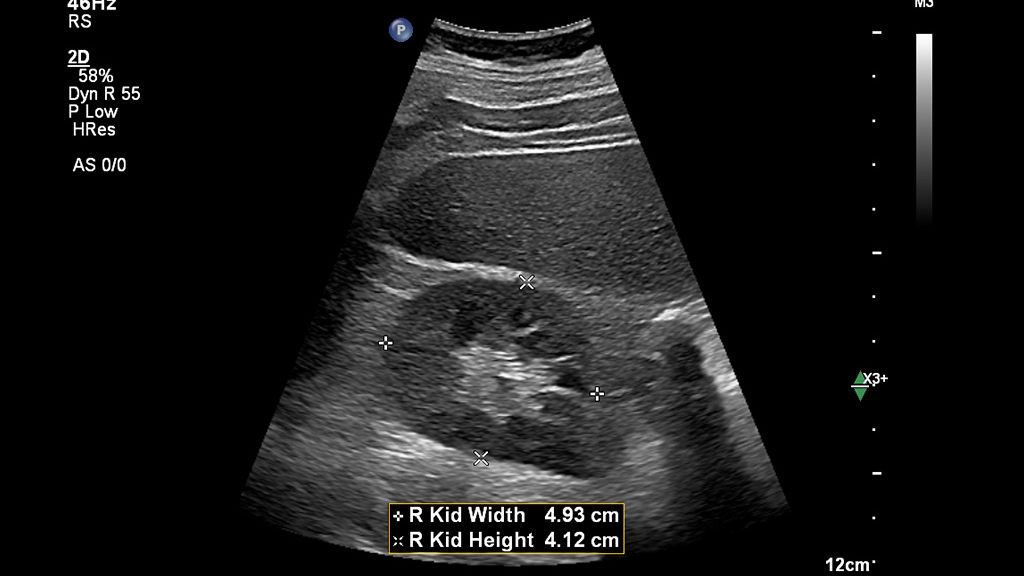

AI-driven Auto Measure Abdomen - Philips